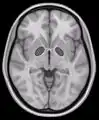

شريحة أفقية لصورة بالرنين المغناطيسي تُظهر الكرة الشاحبة.